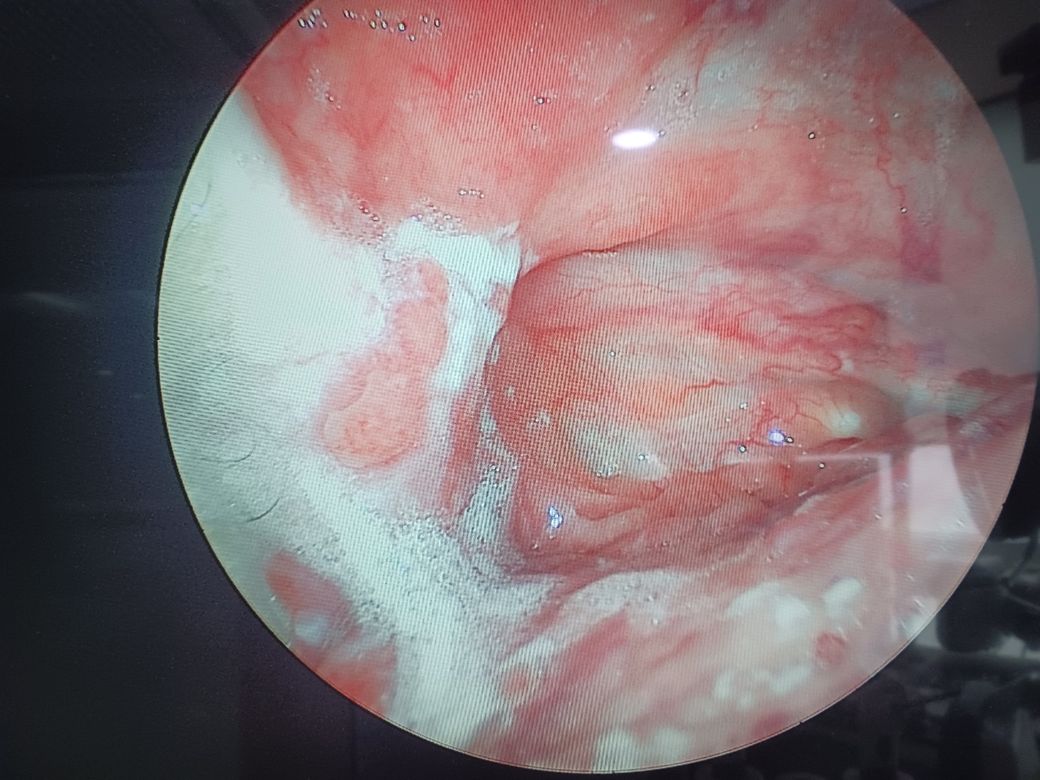

몇주전부터 목에 이물감이느껴지고 삼킬때 목에 뭐가 걸려있는거같아요 병원에서는 흰색가운데 부분이 이상하다고 하던데 사진한번봐주실수 있을까요

• 2번 째 사진